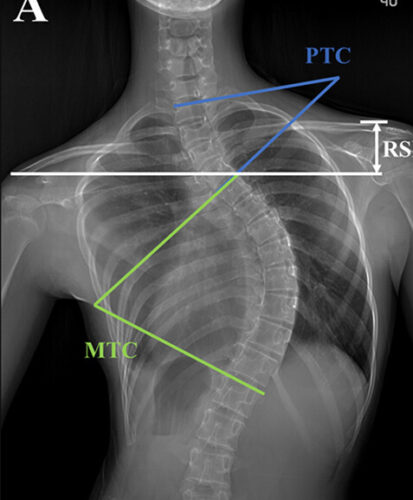

الجنف هو انحناء غير طبيعي للعمود الفقري يأخذ شكل حرف S أو C. هذا الانحناء يؤدي إلى:

الاعوجاج حالة مستمرة ولهذا السب قد تحتاج تدخلًا في مراحل مختلفة من العمر. وبفضل وجود تقنيات التصنيف المعتمدة ، يمكن للأطباء تصميم خطة علاجية مخصصة تضمن تدخلاً جراحيًا عند الضرورة أو العلاج غير الجراحي قبل ذلك، لتفادي الاضطراب في الوظائف التنفسية أو أي أعراض متأخرة. فريقنا المحترف يضم نخبة من الأطباء والمتخصصين الذين يجمعون بين الخبرة والاحترافية لتقديم خطة علاجية شاملة ومخصصة لحالتك، تضمن السيطرة على الانحناء ومنع زيادته.